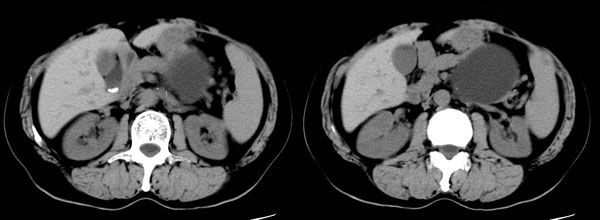

ct平扫加增强扫描:胆囊折叠,壁厚,其内见结石。胰腺体尾部见一5.8x7.5cm囊性肿物,ct值12hu,壁薄,增强扫描未明显强化,胰头不大,强化均匀。

参照ct片,经皮穿刺,抽出透明液体60ml,随后置入引流管引流,囊液细胞学检查阴性,胰酶检查阴性。采用无水乙醇灌注治疗。4天后囊腔闭锁,无液体渗出,予以拔管。

置管后造影,显示囊腔直径约5cm,囊壁光整,正位、双斜位造影均未见造影剂外溢,与胰腺无交通